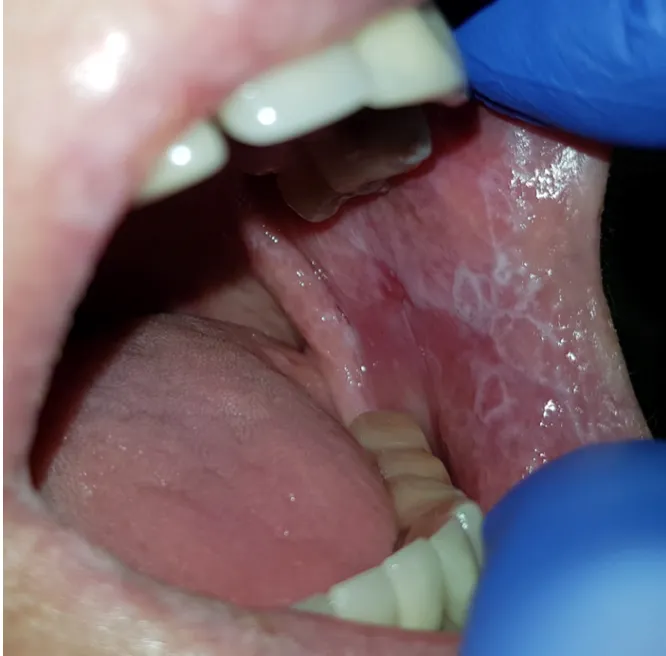

Najczęściej spotykaną postacią liszaja płaskiego jamy ustnej jest postać siatkowata. Charakteryzuje się ona obecnością białych, koronkowatych linii, które często układają się w charakterystyczną siateczkę, znaną jako siateczka Wickhama. Zmiany te najczęściej pojawiają się na błonie śluzowej policzków, ale mogą również występować na języku. Co ważne, ta postać liszaja jest zazwyczaj bezbolesna i często bywa wykrywana przypadkowo podczas rutynowej wizyty u stomatologa. Mimo braku bólu, nie należy jej lekceważyć i wymaga ona regularnej obserwacji.

Znacznie bardziej dokuczliwa i wymagająca natychmiastowej interwencji jest postać nadżerkowa lub wrzodziejąca liszaja płaskiego. Objawia się ona bolesnymi, czerwonymi nadżerkami i owrzodzeniami, które mogą krwawić. Pacjenci z tą postacią często doświadczają silnego bólu i pieczenia, które znacząco utrudniają codzienne funkcjonowanie. Jedzenie, picie, a nawet mówienie stają się wyzwaniem, co prowadzi do znacznego obniżenia jakości życia. Tego typu objawy zawsze powinny skłonić do pilnej wizyty u specjalisty.

- Postać zanikowa: Charakteryzuje się ścieńczeniem i zaczerwienieniem błony śluzowej. Powoduje to jej nadwrażliwość, co może objawiać się pieczeniem i dyskomfortem, zwłaszcza podczas spożywania niektórych pokarmów.